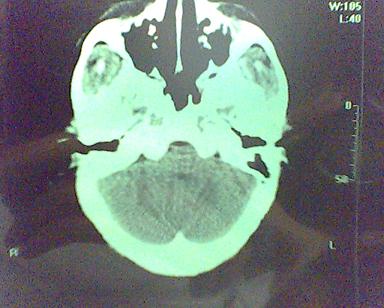

男 31岁 短暂性四肢抽搐 呼叫不应  头胀痛4个多月 无发热 4年前遭棒击头部,当时未到医院检查。余无特殊。病人特穷,未作增强。

这是一个边缘清晰的等密度的囊性占位.密度比较均匀,周围无水肿,我顷向于脑脓肿的可能性大.

右侧乳突蜂房消失,右侧颞叶区囊性占位,水肿不明显,考虑表皮样囊肿或耳源性脑脓肿,+c!。